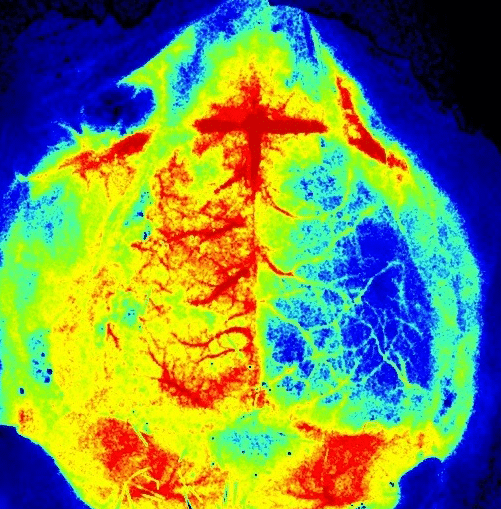

血流灌注成像仪 PeriCam PSI

脑卒中模型 (MCAO)

脑血流量 (CBF) 的变化是许多神经系统疾病的特征,因此是神经科学领域众多研究的焦点。这些研究需要工具来研究这些变化,最好通过无创且实时的方法。 PeriCam PSI System 是一种基于激光散斑对比分析 (LASCA) 技术的血流灌注成像仪。LASCA 为研究微循环提供了的全新手段。它可以实现组织血流灌注的实时可视化,并将动态反应与空间分辨率相结合。它对灌注没有影响,因为不需要直接接触组织,也不需要显影剂或示踪元素。为了进一步提高其可用性,我们开发了专用的应用软件 PIMSoft。PSI 在多种小鼠模型中被广泛用于监测 CBF 和 CBF 的变化,以描述疾病病理和监测治疗效果。

大脑中动脉阻断 (MCAO) 是用于小鼠和大鼠的常用脑卒中模型。将细丝插入动脉以封闭血流一段固定的时间(通常为 30-120 分钟),然后拔除细丝实现再灌注,即会导致缺血性脑卒中 (2), (3), (4), (5), (6), (7), (8), (9), (10)。此时,可以监测皮层血流量,以确保事实上已经诱发脑卒中(1)。 这可以使用传统的激光多普勒灌注监测通过将探头粘到头骨或通过激光散斑对比成像 (LSCI) 来完成,它可以提供脑血流量 (CBF) 的实时图像。

PeriCam PSI 用于表征缺血性脑损伤

Perimed 是第一家对基于激光的微循环成像技术进行商业化的公司,在过去40年内一直是致力于完善这些技术的。PSI 具有独特的功能,可以研究几种模型中的缺血性脑损伤,包括脑卒中、慢性脑灌注不足和创伤性脑损伤。

更大可视区域:整个大脑区域可视化,便于缺血性损伤的确认和表征

高空间分辨率: 提供损伤的精确位置。插入感兴趣区域 (ROI) 可以测量损伤区域,并可用于跟踪损伤恢复情况。